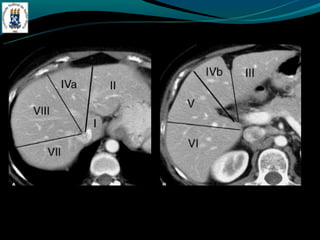

SEGMENTAÇAO DE COUINAUD

FIGADO -Peso: 1,4 –1,7 Kg -Medida transversal 20 - 26 cm -Medida vertical 15 - 21 cm -20 – 25 % do suprimento artéria hepática -75 – 80% do suprimento veia porta